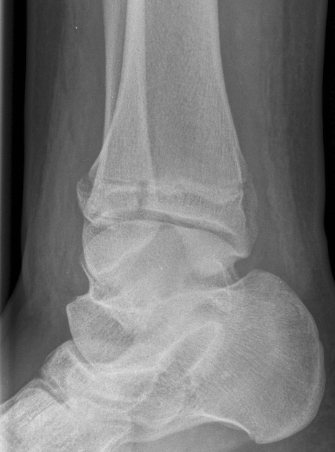

Xray

AP xray: Salter-Harris type III / Tillaux

Lateral xray: Salter-Harris Type II

CT

Coronal images: Salter-Harris type III

Sagittal images: Salter-Harris type II

Axial images: 3 point star